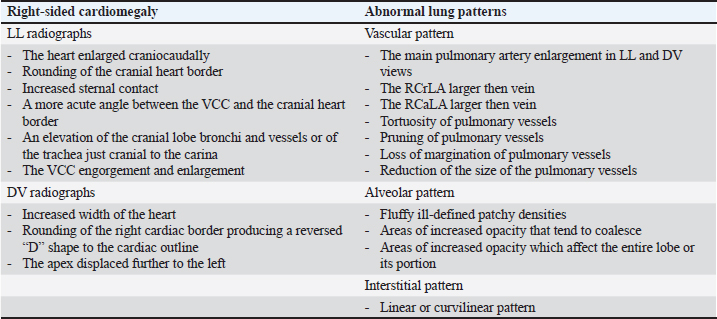

AbstractBackground: Heartworm disease (HWD) represents the pathological consequences of heartworm (HW) (Dirofilaria immitis) infection on different organs and organ systems, primarily the lungs and heart. Radiography can objectively assess the severity of cardiopulmonary disease secondary to HW infection. However, interpreting dogs’ radiographs can be quite challenging with respect to choosing an appropriate radiographic method. Aim: The aim of this article is to review the published literature on radiographic methods, both subjective and objective, emphasizing their advantages and disadvantages. In order to define the feasibility and findings of the used radiographic methods, radiographs (laterolateral-LL and dorsoventral-DV) of dogs (N=40) naturally infected with HWD were retrospectively analysed. Methods: Subjective radiographic assessment included all parameters of abnormal lung patterns and right-sided cardiomegaly in HWD. Objective methods used for the assessment of cardiac size and shape were: modified vertebral heart size (modified VHS), manubrium heart score, sternebral heart size (SHS), thoracic inlet heart size, and cardiac sphericity index (CSI). Blood vessels were measured and expressed in relation to different skeletal structures or the aorta, depending on the blood vessels. Results: While the increased sternal contact, reversed D heart shape, and loss of pulmonary vessel margination were the most feasible subjective parameters, the modified VHS, SHS, and CSI (VHS-LL=10.52 ± 0.97, VHS-DV=10.79 ± 1.12; SHS-LL=9.22 ± 1.04; SHS-DV=9.49 ± 0.96; CSI-LL=0.86 ± 0.08, CSI-DV=0.75 ± 0.07) were the most feasible objective methods. The ratios of the right cranial lobar artery (RCrLA) to the fourth thoracic vertebra (T4) and the fourth rib (4.r) were the most feasible blood vessel measurements (RCrLA/T4=0.27 ± 0.08, RCrLA/4.r=0.89 ± 0.25). In 5% of the dogs, radiographs could only be assessed subjectively. The most prevalent subjective parameters were increased sternal cardiac contact (91.89%), reversed D heart shape (89.65%), RCaLA enlargement (86.67%), and loss of pulmonary vessel margination (84.21%). The main pulmonary artery enlargement in LL, and the areas of increased opacity that tend to coalesce, significantly changed after successful HWD therapy. Conclusion: The most feasible and prevalent subjective parameters were the increased sternal contact, reversed D heart shape, and loss of pulmonary vessel margination. The most feasible objective methods were the modified VHS, SHS, and CSI. Keywords: Heartworm disease, Radiographic methods, Dogs. IntroductionHeartworm disease (HWD) implies heartworm (HW) infection, but also goes beyond this term. Diagnosis of HWD consists of the HW infection detection, and the determination of pathological consequences on relevant organs and organ systems (primarily on the lungs and heart, but also on the kidneys, joints, blood, and immune system) caused by a parasite—HW (Dirofilaria immitis—D. immitis). While the detection of HW infection is based on identifying circulating microfilariae and adult parasite antigen in blood samples, the diagnosis of HWD can require different diagnostic methods depending on the compromised organs or organ systems. The pathological consequences on different organs and organ systems are a result of the pathogenesis of the HWD. Since the parasite resides in the pulmonary arteries, the initial pathological lesion is villous myointimal proliferation (endothelial cell swelling, widening of intracellular junctions, increased endothelial permeability, and periarterial oedema). Endothelial damage further leads to arterial thrombosis, while endothelial permeability and periarterial oedema result in pulmonary infiltrates (neutrophils and eosinophils) and lung consolidation. Pulmonary eosinophilic infiltrates in HWD (eosinophilic bronchopneumopathy, allergic pneumonitis) are considered to be a manifestation of immunologic hypersensitivity caused by the HW (Knight, 1980; Schaub et al., 1981; Keith et al., 1983; Kittleson, 1998; Ware, 2011). When inflammatory pulmonary changes become chronic, their end-stage can be lung fibrosis (Kittleson, 1998). After the parasites die (either naturally or therapeutically), a more intensive host reaction, such as pulmonary thromboembolism (PTE), severe lung tissue damage, shock, and coagulopathy occurs (Kitoh et al., 1994a,b; Kitoh et al., 2001). In addition, severe complications of the HWD may include pulmonary hypertension (PH), right-sided heart failure and caval syndrome. HWD-induced PH is a consequence of increased pulmonary vascular resistance caused by intimal and media thickening of the pulmonary arteries and an obstruction of blood flow in the pulmonary arteries. The aforementioned vascular changes increase the right heart afterload, causing right ventricular hypertrophy and cor pulmonale (Dunn, 2000). Caval syndrome is a severe complication of the HWD, caused by the obstruction of v. cava caudalis (VCC) due to large-scale parasite infestation and their aberrant location towards the right heart (Atkins et al., 1988; Jones, 2016). Besides cardiovascular and pulmonary changes, microfilariae act as circulating antigens in blood, and thus have the potential to stimulate an immunological reaction and form immune complexes, with immune complex depositions in glomeruli or synovial membranes, causing glomerulonephritis or reactive polyarthritis (Dunn, 2000). The complex pathogenesis of the HWD and its pathological changes can be registered by the use of different diagnostic methods. In this article, we will focus on cardiopulmonary manifestations of the HWD, which are by far the most common in clinical practice. Radiography is considered the most objective method of assessing the severity of cardiopulmonary disease secondary to HW infection (AHS, 2025). The aim of the study is to review the literature on the subject of radiographic methods and their features relevant to the HWD, and to retrospectively analyze the feasibility and results of these methods in radiographs of dogs naturally infected with HWD. Literature reviewThoracic radiography is performed in dogs with HWD in order to see the morphology of the lung field and cardiac silhouette, and thus to determine respiratory and cardiovascular pathological changes caused by the parasite. Radiographic changes associated with HWD can be assessed both subjectively and objectively (Table 1). While subjective assessment of radiographs identifies and describes the presence of pulmonary vascular, parenchymal, and interstitial changes, as well as cardiac size and shape, objective radiographic assessment measures and determines cardiac size and shape, as well as the size of blood vessels relevant for HWD. Subjective radiographic assessment shows greater interobserver variability in comparison with objective methods, which are considered to be more reliable for inexperienced veterinarians as well as in questionable cases (Buchanan and Bücheler, 1995; Lamb et al., 2000; Hansson et al., 2005). Table 1. References selected on the basis of radiographic assessment in HW-infected dogs.

Typical vascular abnormalities include a bulging pulmonary artery segment and enlarged lobar pulmonary arteries, with peripheral pulmonary arteries becoming tortuous and truncated (Ackerman, 1987; Kittleson, 1998; Dunn, 2000; Polizopoulou et al., 2000). Arteritis lies at the root of enlarged arteries, to which PH may also contribute. Severe arteritis produces pulmonary artery tortuosity (Kittleson, 1998). Dead parasites act as pulmonary emboli, interrupting blood flow to lung segments, leading to the appearance of suddenly terminated pulmonary arteries, seen as blunted or pruned arteries (Kittleson, 1998). The enlargement of lobar pulmonary arteries, without concurrent venous distension, is strongly suggestive of HWD or other causes of PH (Ware, 2011). The right caudal lobar artery (RCaLA) is most commonly and heavily infested due to the effect of blood streaming toward this artery. Following the RCaLA, the left caudal lobar artery and subsequently, the cranial lobar arteries are the next commonly affected (Kittleson, 1998). Normally on radiographs, the VCC emerges through the diaphragm and slopes slightly cranioventrally towards cardiac caudal margin. It is similar in size to the aorta (Ao), but may get wider towards the heart (Herrtage and Denis, 1997). Enlargement of the VCC has been reported as a radiographic finding of right-sided cardiomegaly (Suter and Lord, 1984). Pulmonary parenchymal abnormalities vary from increased lung densities, seen in dogs with mild-moderate disease, up to generalized densities throughout the lung field (Kittleson, 1998). Parenchymal abnormalities, apparent especially after adulticide therapy, are seen as patchy alveolar densities (Dunn, 2000). Patchy pulmonary alveolar or interstitial infiltrates are the result of oedema, pneumonia, infarction, or fibrosis. Pulmonary opacities may be perivascular (Ware, 2011). Concerning heart remodeling, right ventricular enlargement is a characteristic radiographic feature (Dunn, 2000). This is a secondary change, arising as a consequence of PH. Right heart enlargement is seen in dogs with moderate to severe PH, and is best assessed on either the dorsoventral (DV) or ventrodorsal (VD) radiographic view (Lombard and Ackerman, 1984). Objective radiographic methods in HWD assess overall cardiac size and shape, and the size of blood vessels relevant to HWD in relation to various skeletal structures (intercostal spaces, vertebrae, sternebrae, thoracic inlet (TI), and etc.). The intercostal space method is based on counting the number of intercostal spaces that cover the heart silhouette (Buchanan, 1968; Buchanan and Bücheler, 1995). Although introduced a long time ago, it is still used, and like all other methods has its advantages and disadvantages. It is well known among clinicians and easy to use, because it is directly performed by counting the number of intercostal spaces while observing a dog’s lateral radiograph (LL). A normal heart silhouette has the size of 2.5 to 3.5 intercostal spaces, for deep-chested or wide-chested dogs respectively (Buchanan, 1968; Kealy, 1979; Owens, 1985). However, false negative and positive findings are possible due to thorax conformation, the position of the heart in the thorax, phase of respiration and position of the diaphragm, superimposition of ribs, and imprecise reference points (Buchanan and Bücheler, 1995). In 1995, the vertebral heart size (VHS) was introduced as an objective method, which expresses heart size through long axis (LA) and short axis (SA) normalized to the midthoracic vertebrae, starting from the fourth thoracic vertebra (T4) (Buchanan and Bücheler, 1995). In LL of dogs, the reference point for the cardiac LA is the ventral border of the left mainstem bronchus and the most distant ventral contour of the cardiac apex. This length reflects the combined size of the left atrium and left ventricle. The measured cardiac LA, made by using an adjustable caliper, is then repositioned over thoracic vertebrae beginning with the cranial edge of the T4. The distance to the caudal caliper point is then estimated to the nearest 0.1 vertebra (v). The maximal cardiac SA is measured in the central third region, perpendicular to the cardiac LA axis, and then also repositioned along thoracic vertebrae starting from the beginning of T4. The sum of LA and SA dimensions represent the overall size of the heart expressed as total units of vertebral length to the nearest 0.1 v. In DV or VD radiographs, the maximum LA and SA of the heart are determined with calipers in a similar fashion and measured against vertebrae in the LL radiograph beginning with T4 (Buchanan and Bücheler, 1995; Buchanan, 2000). The determined VHS in normal dogs is 9.7 ± 0.5 v in LL radiographs, and 10.2 ± 1.45 and 10.2 ± 0.83 v in DV and VD, respectively (Buchanan 2000). By using this method many studies have proposed breed-specific VHS reference values (Lamb et al., 2001; Gulanber et al., 2005; Bavegems et al., 2005; Marin et al., 2007; Castro et al., 2011; Jepsen-Grant et al., 2013). The following factors were found to influence mean VHS: interbreed variations, interobserver differences concerning references points of LA and SA, transformation into vertebral unit (v), and anomalies of thoracic vertebrae and intervertebral disc diseases (Hansson et al., 2005; Jepsen-Grant et al., 2013), cardiac cycle and, to a lesser extent, respiratory cycle (Olive et al., 2015). In order to overcome some of these limitations, modifications of this method, concerning the determination of reference points for SA of the heart and the introduction of the VHS unit (the length of one thoracic vertebra), have been proposed (Hansson et al., 2005; Spasojević Kosić et al., 2007; Costanza et al., 2022). The manubrium heart score (MHS) is proposed as the method that can overcome some limitations of the VHS method (Mostafa and Berry, 2017). In this method, the length of the manubrium (M) is used as a reference value to normalize the measurement of the height and width of the cardiac silhouette in right LL and VD thoracic radiographic views. On the LL view, the cardiac LA is measured from the ventral border of the carina to the caudoventral margin of the cardiac apex. The cardiac SA is measured on a line perpendicular to the LA at the widest point of the cardiac silhouette. On the VD view, the cardiac LA is measured from the distance of the right cranial margin of the heart silhouette to the cardiac apex, and the SA heart axis is measured at the widest line perpendicular to the LA. The M length is measured as the maximum M length on the right LL view. The reason why the M of the sternum is selected is that it is relatively prominent, easily identified, and measured on LL radiographs. At the same time, an evenly elongated, bullet-shaped, rectangular, or camel head-neck-shaped M is accepted for the MHS measurement. However, if the M of dogs is abnormal or its cranial edge cannot be identified, the calculation of the MHS is not possible. Established values of the MHS in normal healthy dogs vary from 4.8 ± 0.5 to 5.3 ± 0.8 in LL view, and from 5.4 ± 0.6 to 5.8 ± 0.9 in VD view in large and small dogs, respectively (Mostafa and Berry, 2017). Furthermore, the MHS is recommended as a useful, objective method for heart disease screening in dogs, capable of distinguishing between left-sided and right-sided cardiomegaly (Mostafa et al., 2020). In addition to MHS, the cardiac sphericity index (CSI) is another measure of the shape of the heart, which can be used to assess the globe-shaped heart. It is calculated by dividing the cardiac SA by the cardiac LA. The value of CSI≥1.00 means a near round figure of the cardiac silhouette (Guglielmini et al., 2012). Recently, the sternebral heart scale was proposed for the assessment of heart size in ferrets (Gutiérrez et al., 2022). Upon determination of cardiac LA and SA in radiograph views, the LA and SA of the heart are measured along the sternum, starting at the cranial edge of the fourth sternebra (S4). The sum of the cardiac LA and SA is expressed in sternebral units (s), estimated to an accuracy of 0.1 seconds. Thus, it determines the sternebral heart size (SHS) in this species. This method overcomes the limitation of the MHS caused by the abnormal shape of the M or the impossibility of cranial margin M line identification (Gutiérrez et al., 2022). Although the correlation between heart size and sternebral length was slightly lower compared to the correlation with the vertebral length in dogs (Buchanan and Bücheler, 1995), to the best of our knowledge, no study on the subject of the normal SHS in dogs has been published yet. First proposed as a reference point to assess tracheal diameter in brachycephalic and non-brachycephalic dogs (Harvey and Fink, 1982; Mostafa and Berry, 2022), the TI has recently been assessed as a unit for measuring thoracic inlet heart size (TIHS) (Marbella Fernández et al., 2023a). In this study, the TIHS has proved to be a simple and accurate method for measuring heart size, which overcomes some limitations seen in previously mentioned methods, such as vertebral or M malformations, and variations due to dog’s size and breed. Reference points for the cardiac LA and SA in this method are like the ones described for the VHS. Upon being measured the cardiac LA and SA are summed and divided by the corresponding TI length. The TI, defined as the minimum length of the TI, is determined as the distance between the cranio-ventral aspect of the first thoracic vertebra and the cranio-dorsal margin of the M at its highest point. The mean TIHS value for normal dogs is 2.86, and a TIHS value above 3.2 is considered to be an increased heart size in dogs (Marbella Fernández et al., 2023a). Besides methods based on linear determination of cardiac size through its LA and SA, which are then expressed by different skeletal structures, methods based on the estimation of cardiac areas have also been investigated. One of these modalities for cardiac size evaluation is the ratio between cardiac and thoracic areas (Torad and Hassan, 2014). Determination of the cardiothoracic ratio derived from LL thoracic radiographs (Empel and W, 1974) or on both LL and VD radiographs after peak inspiration and expiration (Castro et al., 2011; Torad and Hassan, 2014). Another way of assessing heart size is to compare the heart area to the T4 body area (So et al., 2024). These methods showed not only a correlation with VHS (Azevedo et al., 2016; So et al., 2024), but also, and to a higher extent, with the cardiac volume measured by computed tomography (So et al., 2024). However, these methods are complicated and require specific software, not always available in clinical practice. In addition, thoracic cavity conformation varies in different dog breeds, and individual changes in healthy and diseased animals (Buchanan and Bücheler, 1995; Castro et al., 2011; Torad and Hassan, 2014) make these methods of limited use. Blood vessels relevant to HWD (RCrLA, RCaLA, VCC) can also be assessed objectively, by comparing them with different skeletal structure, or, in case of the VCC, with the Ao. The width of the RCrLA on a LL view in normal dogs should not exceed the narrowest diameter of the 4th rib (4.r). On DV radiographs, the width of the RCaLA is normally not larger than the 9th rib (9.r) at the level of their intersection (Herrtage and Denis, 1997; Ware, 2011). Furthermore, ratios of RCrLA/4.r≥ 1.08, and RCaLA/9.r≥ 1.10 indicate the presence of PH, and thus show potential as a preliminary screening tool for PH in HW-infected dogs (Falcon Cordon 2024a). The measurement of VCC size and its ratio towards other fixed-sized surrounding structures, such as the length of vertebrae at the level of tracheal bifurcation, the descending Ao, and the width of the 4.r can help in the detection of right-side heart disease in dogs (Arya et al., 2021). The diameter of VCC should be considered normal in a dog with a ratio of VCC/Ao < 1.00, VCC/ v < 0.80, or VCC/4.r < 2.25 (Lehmkuhl et al., 1997). Material and MethodsData used in this study related to client-owned dogs in which HW infection was identified. For this purpose, the medical records of these dogs were reviewed with the collection of all data relevant for the retrospective radiographic analyses. The material for this study included radiographs of 40 dogs naturally infected with D. immitis. There were two criteria for this study. The first one was a complete HW infection diagnosis performed in these dogs (detection of antigen of adult parasite D. immitis and modified Knott test). The second criterion was that the dog had either LL or both (LL and DV) radiographs recorded without the use of sedation or anesthesia. While in 4 dogs only LL radiographs were available, in all others, both LL and DV radiographs were used for analyses. The dogs were of different age, gender, and breed. The average age of the dogs was 6.36 ± 3.68 years, and there were 12 females and 28 males belonging to different breeds (German Shepherd, Belgian Shepherd, Labrador Retriever, Golden Retriever, Rottweiler, Boxer, Dobermann, American Staffordshire Terrier, American Pit Bull Terrier, Great Dane, Dogo Argentino, Cane Corso, Hungarian Vizsla, German Hunting Terrier, Breton Spaniel, and mixed-breed dogs of small and medium size). For 8 out of these 40 dogs, radiographs of both projections (LL and DV) were available at the moment of the HWD diagnosis (before therapy) and at the end of successful therapy (after therapy). The alternative therapy (doxycycline and ivermectin) (Spasojević Kosić et al., 2024) was used as the HW infection therapy in all eight dogs. The dog was considered cured of HWD if clinical signs have disappeared and if no D.immitis antigenemia and microfilariaemia have been detected. At that time the post-treatment radiographs had been recorded. Thoracic radiographs were obtained using Eickemeyer Hiray Plus, Porta 100HF, with the exposure settings 46/2,5 kVp/mAs - 80/2,5 kVp/mAs, with a focal film distance of 75 cm (Primax flm RTG - G, 30x40, and DR system - Exam VueDuo). Each radiograph was submitted to subjective and objective assessment. Any difficulties which disabled predefined methodology of subjective parameters identifications and of objective measurements were considered as feasibility limitation criteria. All radiographic assessments were done by an experienced veterinary cardiologist. The radiographic assessments were done after being triple check before the final decision. Parameters relevant for subjective radiographic assessment were classified as radiographic features for right-sided cardiomegaly and abnormal lung patterns (Table 2). Table 2. Specific parameters of cardiomegaly and abnormal lung patterns in the subjective radiographic assessment for the HWD.